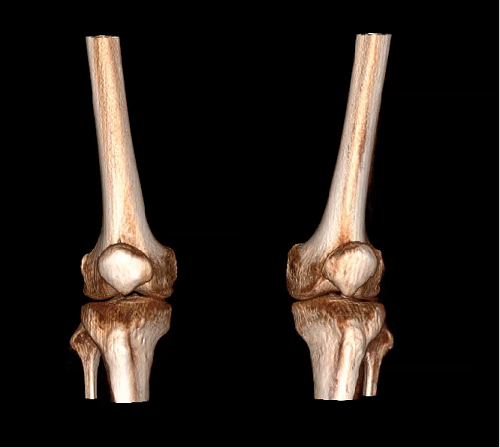

对于WR-3D技术的问世,主要解决了两大核心问题:1、解决了普放DR漏诊率高的现状,常规DR设备仅有某一角度的二维影像、密度信息极差,而WR-3D能获得更丰富的诊断信息,多角度拍摄三维重建影像,任意角度任意切面以及高敏感的密度信息;2、解决了CT无法获得立位(负重位)的三维影像,WR-3D无论是在断层图像重建、MPR多平面重建、VR体绘制都有着优异的表现,而对于临床诊断尤其是骨科,负重位的影像更具有临床价值。患者在负重位状态下肌肉状态、关节间隙及骨骼力线等都与患者平躺时是明显不同的。因此WR-3D在术前精准规划与术后精准评估方面有其非常重要的临床价值。

VR体绘制图像